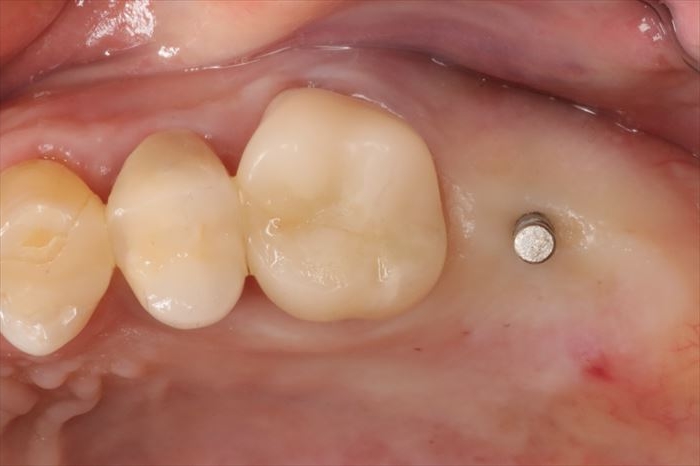

ヒーリングキャップを締結しました。

歯肉切開を伴わないフラップ(歯肉弁)レス埋入オペではオペ終了時に止血も完了します。

切開を伴わないため、術後の痛みが無かったり、あっても最小限であることが多いです。

ただしフラップレスオペは不可視部分での処置が増えますので術者の経験・判断力が必要です。

骨の形や歯肉の形態によってフラップレスオペの可否がありますので、すべてのケースで適用は出来ません。